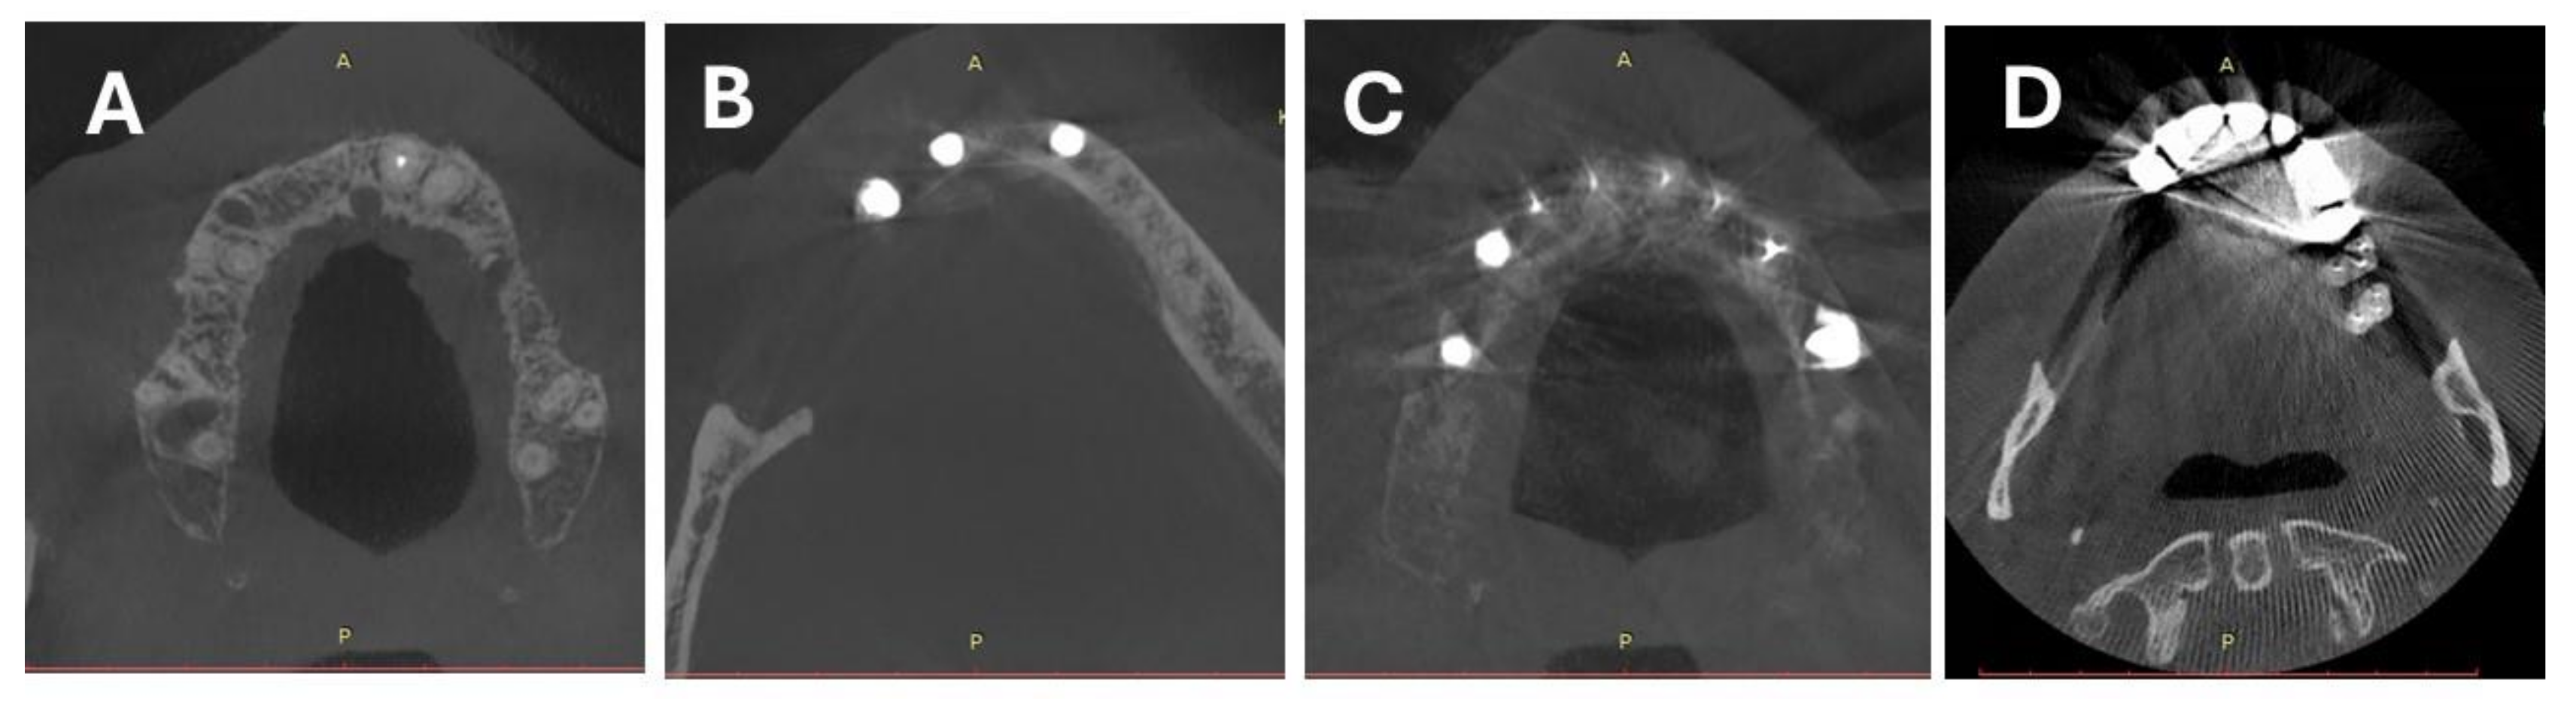

2.2. CBCT Scanning Protocol and Image Reconstruction

2.3. Objective Image Quality Assessment

2.4. Subjective Image Quality Assessment